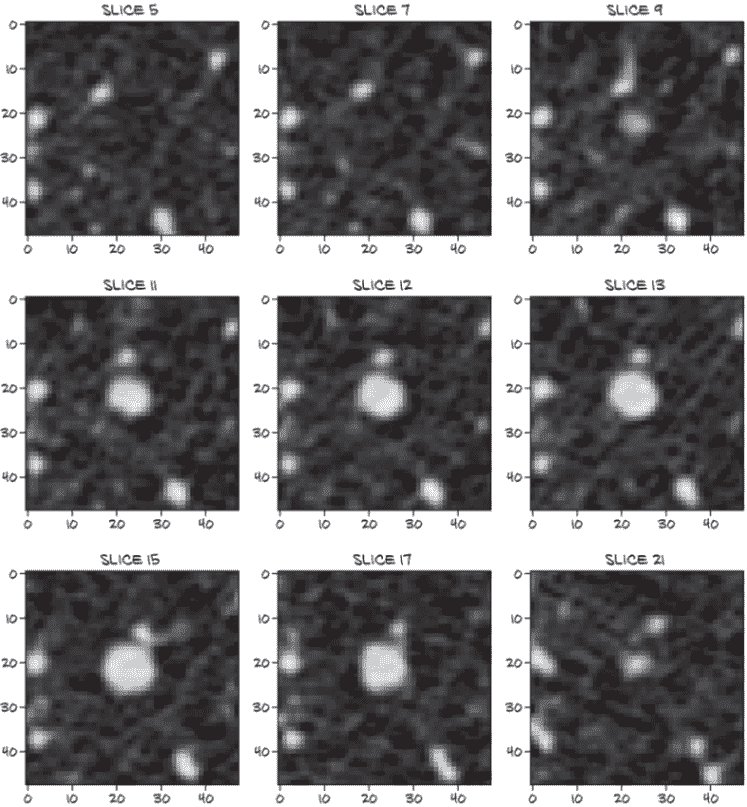

第 3 步(分组)将生成数据,第 4 步(分类)将消耗类似于图 9.6 中包含肿瘤顺序横截面的图像。这幅图像是(潜在恶性,或至少不确定)肿瘤的近距离视图,我们将训练第 4 步模型识别,并训练第 5 步模型将其分类为良性或恶性。对于未经训练的眼睛(或未经训练的卷积网络)来说,这个肿块可能看起来毫无特征,但在这个样本中识别恶性的预警信号至少比消耗我们之前看到的整个 CT 要容易得多。我们下一章的代码将提供生成类似图 9.6 的放大结节图像的例程。

图 9.6 CT 扫描中肿瘤的近距离、多层切片裁剪